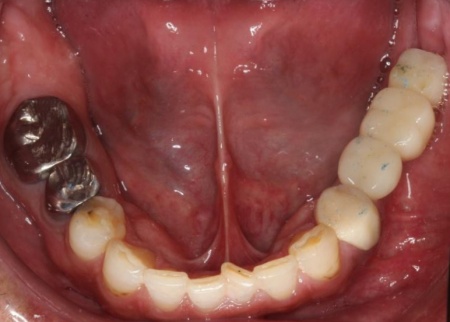

治療後

他院で治療を行った左下奥歯3本のインプラントは、土台をそのまま活かして人工歯だけ作り直し、噛み合わせを調整します。

左下奥歯1本、右下奥歯2本に装着されていた古い被せ物はすべて外し、ジルコニアクラウンと交換しました。